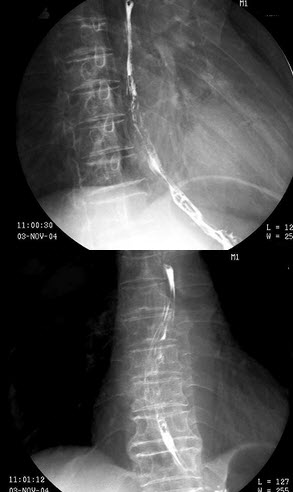

28、单项选择题

男,65岁,腰背部疼痛1月余,结合图像,最可能的诊断是()

A.脊椎结核

B.椎体压缩骨折

C.脊椎退行性变

D.脊椎转移瘤

E.L2~L3椎间盘炎